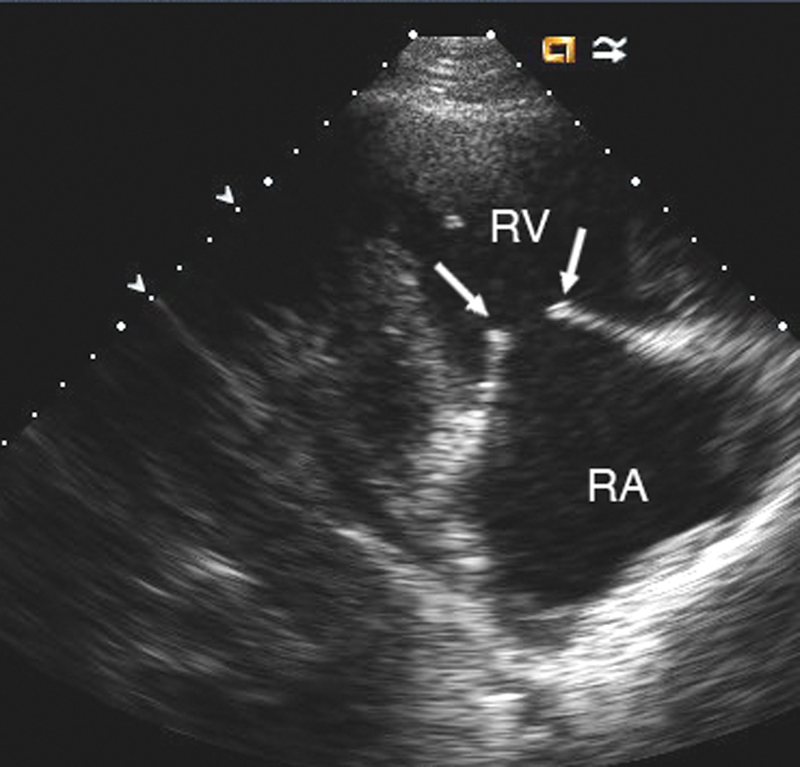

فحوصات تشخيصية لبعض امراض القلب والشرايين التاجية